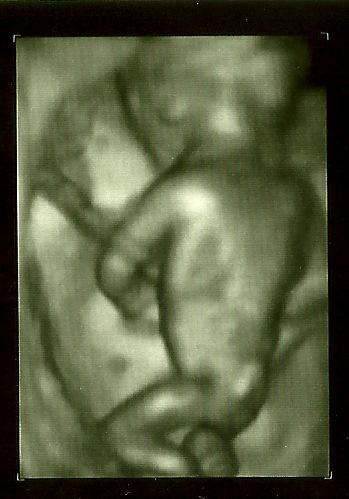

Ich war gestern außerplanmäßig bei meiner FÄ, weil ich am Freitag beim Niesen einen Riss im Unterleib verspürte, als habe mich jemand in der Mitte durchgeschnitten. Mir blieb kurz die Luft weg . Eigentlich wäre ich erst nächsten Montag dran gewesen, aber da ich auch noch nen fiesen Darmvirus hatte (ich nehme momentan auch alles mit, ein Herpes löst den nächsten ab), wollte ich mal schauen lassen. Ich war nur 5 Minuten dran, kurzer Schall (mit Outing, US-Bild siehe unten) nix ausgemessen, FÄ meinte, alles paletti, nächster Termin Anfang Juli. Jut, soll mir recht sein. Gefreut hat mich, dass sie noch kurz auf 3D geschaltet hat, so habe ich endlich ein plastisches Bild vor Augen. Auch ein Rücken kann entzücken. :-) Mein Mann meinte gleich, dass man doch daran das Geschlecht schon erkennen könnte, so ein Popöchen und so ein Kreuz hätten doch nur russische Kugelstoßerinnen... Wie auch immer, ich bin Viele Grüße, Gapsy.

Bild zu Vorzeitige VU mit 3D-Bild - Forum für November - Mamis

wow echt geiles bild - ich bin begeistert... und schön das alles gut ist und für deine weiteren wehwehchen gute besserung glg steffi